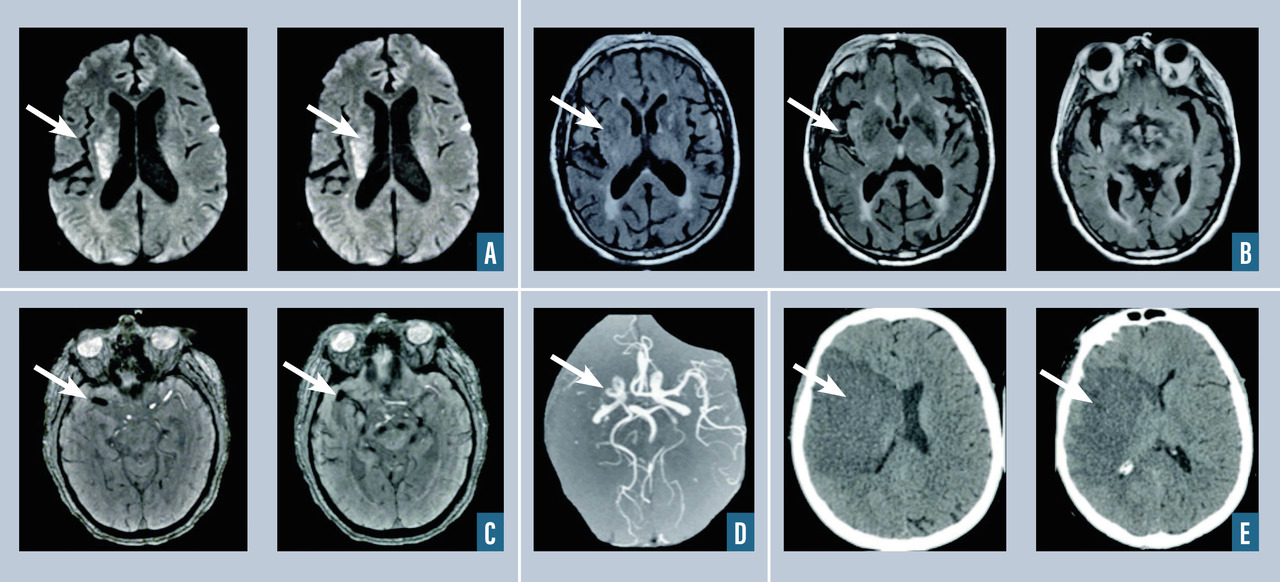

La thrombose veineuse cérébrale correspond à l’occlusion d’un ou de plusieurs sinus veineux cérébraux et/ou des veines corticales (fig. 3 ). On distingue la thrombose veineuse cérébrale sans lésion parenchymateuse, responsable d’un tableau d’hypertension intracrânienne, et la thrombose veineuse cérébrale avec œdème cérébral (« infarctus veineux ») ou avec hématome cérébral, responsable d’une présentation clinique souvent bruyante pouvant associer des convulsions, un déficit neurologique focal, voire un coma. L’imagerie cérébrale met en évidence des signes directs de thrombose sous la forme d’une hyperdensité spontanée du sinus ou de la veine sur le scanner cérébral sans injection (signe du sinus spontanément hyperdense ou de la corde dense) ou en montrant sur l’IRM un hypersignal en T1 et en T2 du sinus thrombosé. Les séquences injectées veineuses (en IRM ou en angioscanner) montrent l’absence d’opacification ou l’opacification partielle du sinus occlus du fait de la présence du thrombus. L’IRM cérébrale avec séquences veineuses (VRM) et l’angioscanner veineux ont actuellement une sensibilité et une spécificité relativement proches pour le diagnostic de thrombose veineuse cérébrale. Les signes indirects de thrombose veineuse cérébrale sont la présence d’un « infarctus veineux » ou d’une hémorragie cérébrale ou méningée sulcale, qui sont des conséquences possibles de la thrombose veineuse cérébrale.